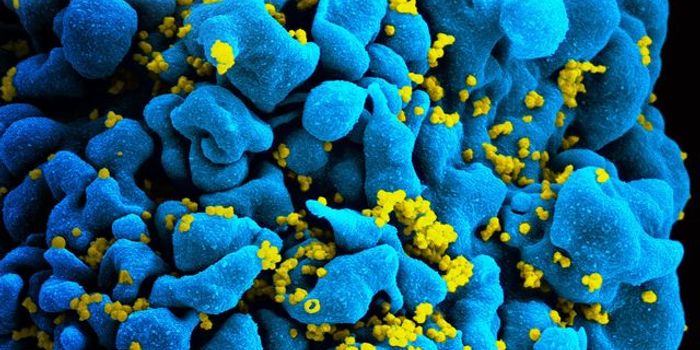

AUG 24, 2020ImmunologyOnce in the body, HIV tracks down T cells that bear the CD4 receptor. It attaches to these immune cells, fusing itself w ...